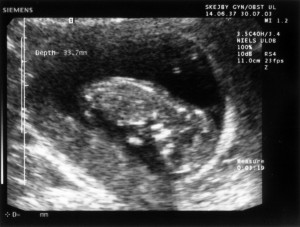

Ultralydsskanning den 30. juli 2003

Vi har i dag været på Skejby Sygehus og få foretaget en ultralydsskanning af baby. Der var kun én (pyh)! Baby blev målt og gennemset for eventuelle misdannelser. Der blev set efter at kraniet var begyndt at blive dannet og at der var to hjernehalvdele. Vi så to arme og to ben og der var fem fingre på den hånd vi så. Vi så også hjertet slå. Til sidst blev der blev målt bredden på nakkenfolden for at vurdere risikoen for mongolisme. Man kan læse mere om ultralydsskanningen her.

Konklussionen var, at alt var som det skulle være, men baby selv var ikke tilfreds. Den lå og sparkede og slog omkring sig og tog sig til hovedet.

Du kan se de billeder vi fik fra skanningen herunder.